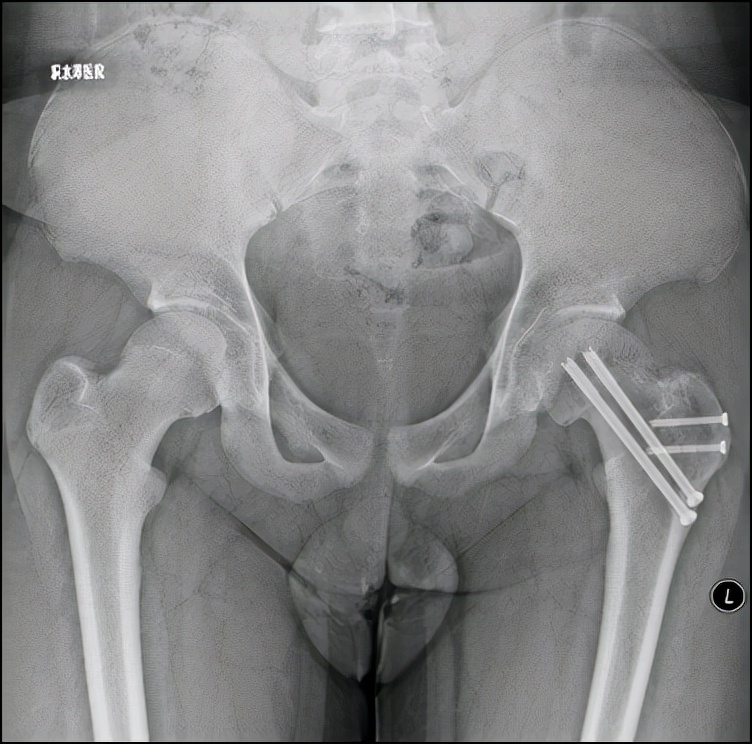

病例1 髋关节外科脱位,改良Dunn截骨,术后2年,X线示位置良好,无股骨头缺血坏死

1998年,北京积水潭医院小儿骨科在国内首先报道使用Russell牵引结合内固定治疗股骨头骺滑脱,在文中提出“对于急性滑脱,持续牵引逐渐内旋复位是可能的”;2012年开始应用髋关节外科脱位改良Dunn截骨来治疗重度SCFE;2018年在前期工作的基础上,开展应用股骨头骺内血供监测来实时监控术中股骨头骺血供;2019年开始应用在机器人辅助下行重度SCFE的经皮螺钉固定,并承担北京市医管中心专项项目:中重度股骨头骺滑脱治疗的临床研究。